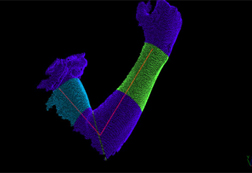

特集 ハンディ3Dスキャナーをリハビリで利用する

3. 手の状態を3Dで調べる。体積や図面も作成できる。計測時間は数秒間。

|

|

|